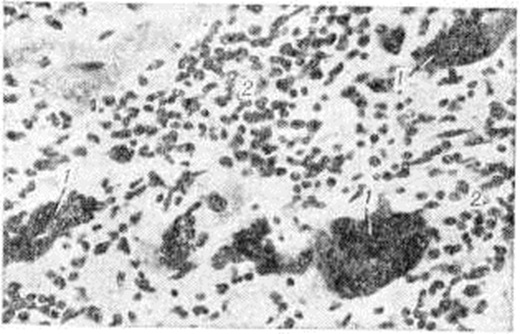

По характеру воспалительной инфильтрации (пролиферативный компонент воспаления) при интерстициальном (межуточном) Миокардит различают очаговый и диффузный варианты. При первом варианте клетки воспалительного инфильтрата располагаются в виде более или менее крупных, но ограниченных гнёзд (рисунок 4). При втором варианте клетки воспалительного инфильтрата диффузно пронизывают межуточную ткань миокарда, раздвигая сердечные мышечные волокна (рисунок 5), располагаясь вдоль них и охватывая различные по протяжённости участки миокарда. При диффузном Миокардит не обязательно тотальное поражение, охват воспалением всей массы миокарда, что бывает при острейшем, бурно развивающемся Миокардит Большей частью воспаление, даже диффузное, имеет мозаичный характер, поражая иногда избирательно или преимущественно субэндокардиальные слои миокарда. Можно предположить, что в начале развития такого Миокардит наблюдается расстройство микроциркуляции и проницаемости в терминальном сосудистом русле. Этот период, по-видимому, не бывает длительным и сменяется нарастающими экссудативными и пролиферативными процессами в строме миокарда.

Экссудативный компонент представлен жидкой частью крови и её форменными элементами в различных соотношениях. Преобладание серозного экссудата с небольшим количеством лейкоцитов приводит к развитию острого серозного Миокардит, встречающегося при токсико-инфекционных поражениях миокарда различной этиологии. При этом пучки мышечных волокон раздвинуты серозным экссудатом, содержащим небольшое количество клеток крови, чаще всего — сегментоядерные лейкоциты. Наблюдаются случаи экссудативного Миокардит с преобладанием эозинофилов в экссудате и инфильтратах. Эозинофильный Миокардит нередко является частью синдрома Леффлера и сопровождается эозинофилией и эозинофильной инфильтрацией органов — лёгких, селезёнки и другие (смотри полный свод знаний Леффлера синдром). К клеткам экссудата иногда присоединяются клетки лимфогистиоцитарного инфильтрата из межуточной ткани сердца. Клетки инфильтрата частично трансформируются в клетки плазмоцитарного ряда, и иногда инфильтрат состоит (в основном) из плазматических клеток (смотри полный свод знаний); в этих случаях можно говорить о плазмоцитарном Миокардит (рисунок 6). При длительном течении Миокардит нарастают процессы фиброплазии за счёт размножения фибробластов межуточной ткани сердца и фиброцитарного превращения гистиоцитов. В результате очаг воспаления замещается рубцовой тканью и развивается миокардитический кардиосклероз.